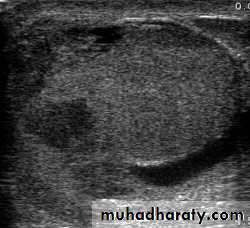

TUMOURS OF THE TESTES

Most testicular neoplasms are malignant

It is one of the most common forms of cancer in young men.Maldescent predisposes to malignancy

testicular lump which is usually painlesssensation of heaviness occurs when the testis is two or three times its normal size

The testis is enlarged, smooth, firm and heavy

Secondary hydrocele

U/S scanning of the testis